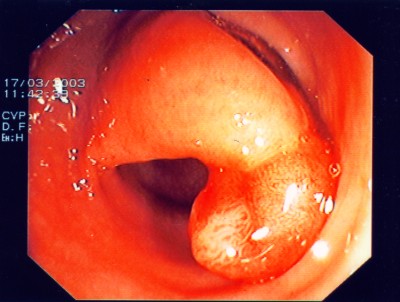

Noch gutartiges Gebilde des Mastdarmes mit schweren Zell- veränderungen. Hier ist eine den Schließmuskel erhaltende Operation möglich - transanale mikroskopische Tumorentfernung (TEM).